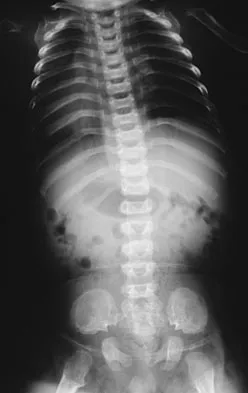

Where is the underlying defect in a rhizomelic dwarf with the findings shown in Figure 5?

Explanation

The radiograph shows the typical findings of achondroplasia. The defect is in fibroblast growth factor receptor 3. The pedicles narrow distally in the lumbar spine. The pelvis is low and broad with narrow sciatic notches and ping-pong paddle-shaped iliac wings. This is often called a champagne glass pelvis. Type I collagen abnormalities are typically found in osteogenesis imperfecta, and type II collagen defects are found in spondyloepiphyseal dysplasia and Kneist syndrome. COMP is defective in multiple epiphyseal dysplasia. Sulfate transport defects are seen in diastrophic dysplasia. Johnson TR, Steinbach LS: Essentials of Musculoskeletal Imaging. Rosemont, IL, American Academy of Orthopaedic Surgeons, 2004, pp 809-812.